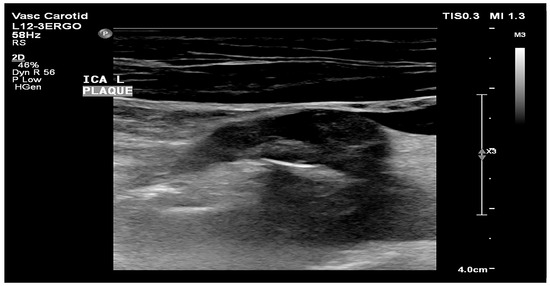

- Atherosclerotic plaque—during the ultrasound examination, the best possible image projection in B-mode presentation was selected with the entire atherosclerotic plaque visible—the image was not enlarged or brightened—according to the accepted standardization. The image of the plaque was recorded on a photograph. Then, to assess the atherosclerotic plaque, images from the ultrasound examination were used to analyze its structure on the GSM scale.

- Images of the visible atherosclerotic plaque in the carotid artery.

2.3.2. Image Standardization

2.3.3. Calculation of the GSM Value of Atherosclerotic Plaques